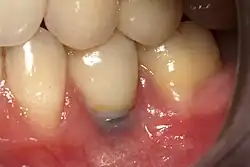

Beyond the possibility of mechanical failure[98] which may be due to poor prosthetic fitment, wear and tear, or user-induced actions such as bruxism, dental implants are also subject to peri-implant mucositis and peri-implantitis, where gum tissue and bone mass around the implant are resorbed, and the implant gradually becomes loose, and has to be removed.[99][100] In addition, although titanium is generally well tolerated by the body, there have been cases where the build-up of titanium particles released by the implant may cause systemic inflammatory response.[101] Because there is no dental enamel on an implant, it does not fail due to cavities like natural teeth. While large-scale, long-term studies are scarce, several systematic reviews estimate the long-term (five to ten years) survival of dental implants at 93–98 percent depending on their clinical use.[15][16][17] During initial development of implant retained teeth, all crowns were attached to the teeth with screws, but more recent advancements have allowed placement of crowns on the abutments with dental cement (akin to placing a crown on a tooth). This has created the potential for cement, that escapes from under the crown during cementation to get caught in the gingiva and create a peri-implantitis (see picture below). While the complication can occur, there does not appear to be any additional peri-implantitis in cement-retained crowns compared to screw-retained crowns overall.[102] In compound implants (two stage implants), between the actual implant and the superstructure (abutment) are gaps and cavities into which bacteria can penetrate from the oral cavity. Later these bacteria will return into the adjacent tissue and can cause periimplantitis.